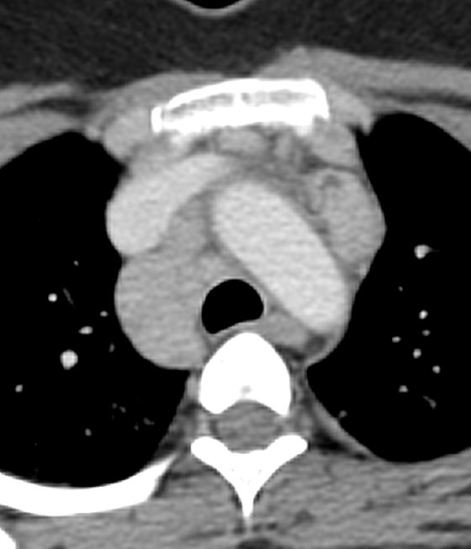

Frontal radiograph of the right hemithorax shows a relatively well defined approximately 2 cm sized oval soft tissue density nodule in the right middle zone. No calcification or cavitation. There is no other nodule. No effusion. No suspicious bone lesion.

Case courtesy of Dr Ayush Goel, <a href=”https://radiopaedia.org/”>Radiopaedia.org</a>. From the case <a href=”https://radiopaedia.org/cases/29150″>rID: 29150</a>

Note that the description of the nodule should always include its shape (round/oval, spiculated, lobulated etc), and presence or absence of cavitation and calcification. Unless the nodule demonstrates certain findings consistent with a benign etiology, it should be labelled as indeterminate and should be further evaluated with a CT/biopsy.